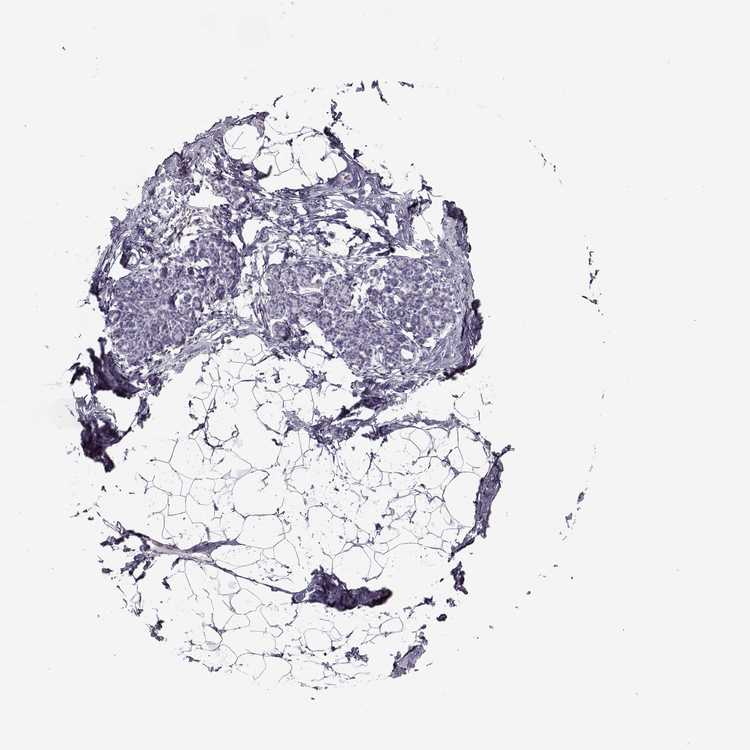

BREAST - Antibody stainingi

Antibody staining in the annotated cell types in the current human tissue is reported as not detected, low, medium, or high, based on conventional immunohistochemistry profiling in selected tissues. This score is based on the combination of the staining intensity and fraction of stained cells.

Each image is clickable and will lead to virtual microscopy that enables deeper exploration of all samples and also displays staining intensity scores, fraction scores and subcellular localization as well as patient and tissue information for each sample.

Antibody HPA005459Antibody CAB010877

Adipocytes Not detectedNot detected

Glandular cells Not detectedNot detected

Myoepithelial cells Not detectedNot detected